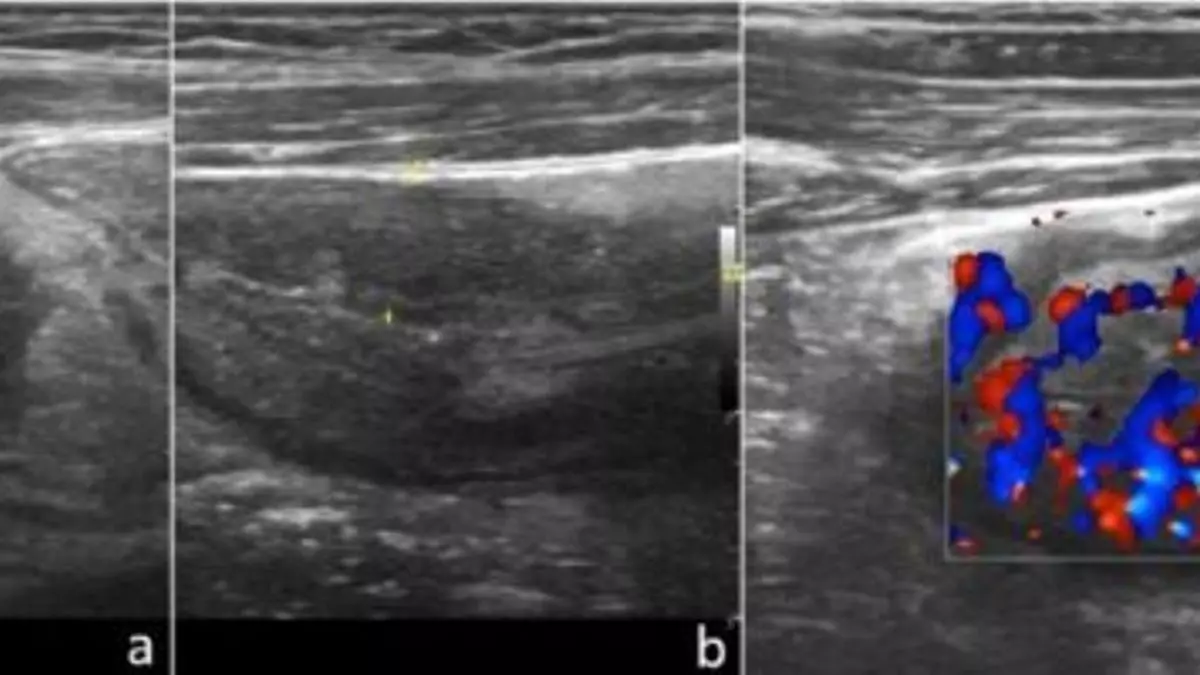

Varias ecografías. / l.o.

La última noticia sobre la privatización de la sanidad pública madrileña ha sido el escándalo de la privatización de las ecografías del hospital La Paz adjudicando su realización a una clínica privada de la que es consejero Rafael Catalá, exministro del Partido Popular en Gobiernos de Mariano Rajoy. Resulta sorprendente la normalidad con que los votantes de Madrid están asistiendo a la destrucción paulatina de un servicio esencial sin que se echen las manos a la cabeza. En la Comunidad de Madrid existe un riesgo cierto de que en unos años el modelo sanitario sea el mismo que hay en países como EEUU, donde los seguros privados han convertido a la sanidad en una jungla en el que quien no tenga seguro privado es dejado en las puertas de un hospital sea cual sea su gravedad. Por no hablar del ya muy lejano excelente sistema sanitario inglés, modelo estudiado por los precursores de sistema de salud español, destrozado por el thatcherismo del años 80.